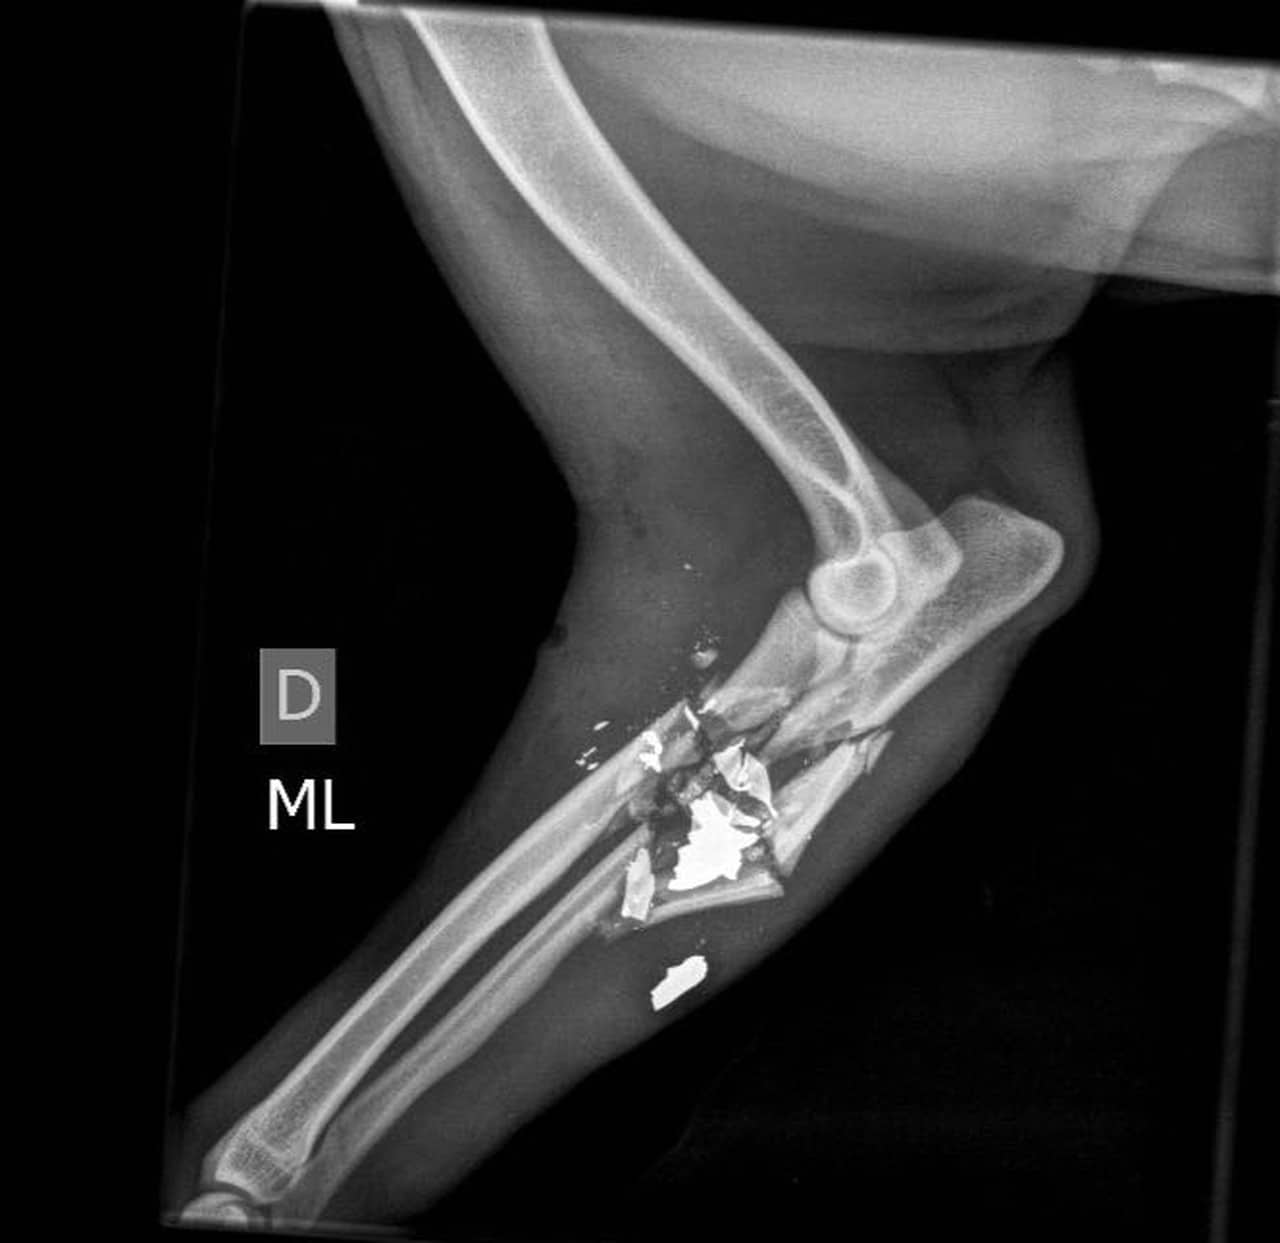

Ele acabou sendo atingido por uma bala perdida durante um confronto na Barreira do Vasco, na Zona Norte do Rio. Infelizmente, isso lhe custou sua pata dianteira, a qual foi amputada.

Os veterinários Luiz Eduardo Castro e André Carneiro, da Sociedade União Internacional Protetora dos Animais (Suipa) chegaram a fazer uma cirurgia de reconstrução, mas infelizmente não houve sucesso. Pelo menos, Bruno passa bem, segundo revelou um dos veterinários sobre o caso.